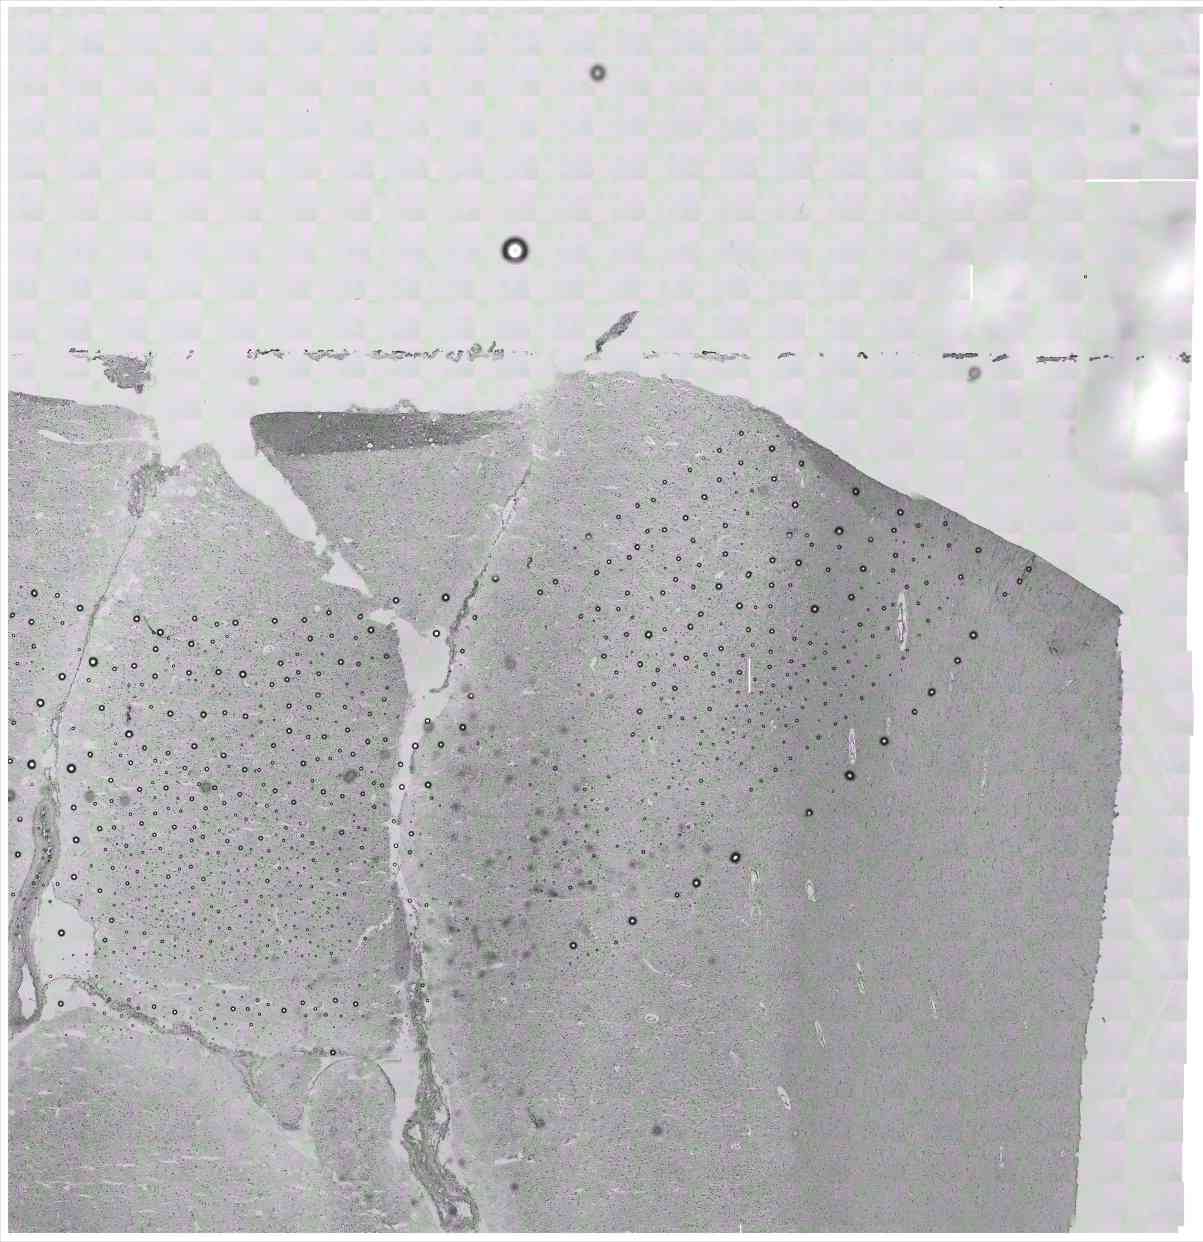

Chip 019 Well C2